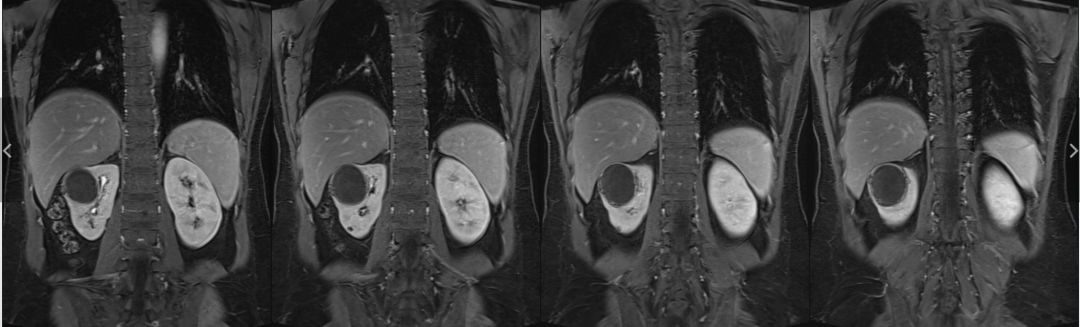

病例1女性,60岁主诉:反复左

病例2女,41岁,主 诉:体检发现右侧肾占位1天余。现 病 史:缘患者于1天因血压升高来我院就诊,体检发现右侧肾占位,

既 往 史:平素健康状况:良好,患者既往有高血压病史2年余,最高

影像表现为:右肾囊性肿块,肾周无软组织及渗出影,增强囊壁轻度强化,囊内弥散受限明显,不强化,周围有出血